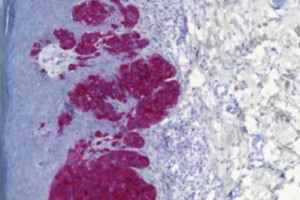

Uveální melanom patří mezi vzácné nádory s omezenými léčebnými možnostmi. Tebentafusp je první lék s unikátním mechanismem účinku, který dokázal prodloužit celkové přežití u pacientů s diseminovaným uveálním melanomem. Seznamte se s mechanismem účinku, s výsledky recentní studie i doporučením pro praxi.